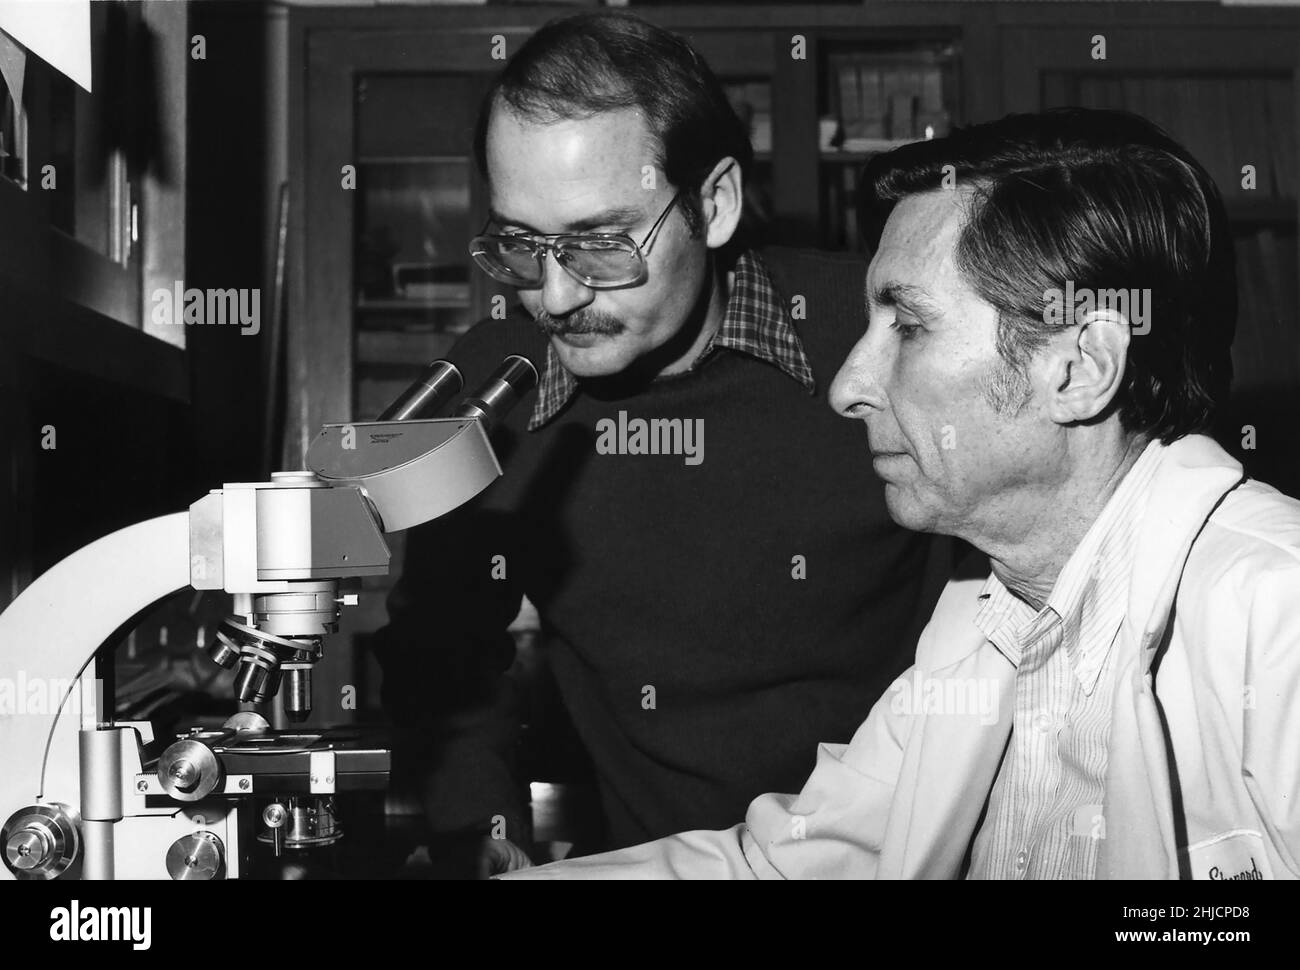

Dieses Bild aus dem Jahr 1977 zeigt die Mikrobiologen Joseph E. McDade (links) und Charles C. Shepard (rechts), die den Erreger isolieren, der den Ausbruch der Legionäre 1976 auf einer Tagung der American Legion in Philadelphia verursacht hatte. Sie stellten fest, dass die Ursache eine Art von Bakterien war, die sie Legionella pneumophila nannten. Stockfotohttps://www.alamy.de/image-license-details/?v=1https://www.alamy.de/dieses-bild-aus-dem-jahr-1977-zeigt-die-mikrobiologen-joseph-e-mcdade-links-und-charles-c-shepard-rechts-die-den-erreger-isolieren-der-den-ausbruch-der-legionare-1976-auf-einer-tagung-der-american-legion-in-philadelphia-verursacht-hatte-sie-stellten-fest-dass-die-ursache-eine-art-von-bakterien-war-die-sie-legionella-pneumophila-nannten-image458814420.html

Dieses Bild aus dem Jahr 1977 zeigt die Mikrobiologen Joseph E. McDade (links) und Charles C. Shepard (rechts), die den Erreger isolieren, der den Ausbruch der Legionäre 1976 auf einer Tagung der American Legion in Philadelphia verursacht hatte. Sie stellten fest, dass die Ursache eine Art von Bakterien war, die sie Legionella pneumophila nannten. Stockfotohttps://www.alamy.de/image-license-details/?v=1https://www.alamy.de/dieses-bild-aus-dem-jahr-1977-zeigt-die-mikrobiologen-joseph-e-mcdade-links-und-charles-c-shepard-rechts-die-den-erreger-isolieren-der-den-ausbruch-der-legionare-1976-auf-einer-tagung-der-american-legion-in-philadelphia-verursacht-hatte-sie-stellten-fest-dass-die-ursache-eine-art-von-bakterien-war-die-sie-legionella-pneumophila-nannten-image458814420.htmlRM2HJCPD8–Dieses Bild aus dem Jahr 1977 zeigt die Mikrobiologen Joseph E. McDade (links) und Charles C. Shepard (rechts), die den Erreger isolieren, der den Ausbruch der Legionäre 1976 auf einer Tagung der American Legion in Philadelphia verursacht hatte. Sie stellten fest, dass die Ursache eine Art von Bakterien war, die sie Legionella pneumophila nannten.